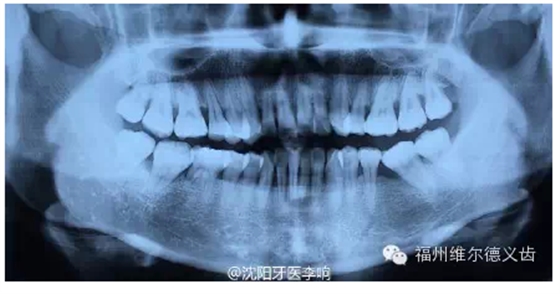

你說種牙太貴我不鑲了,我挺著,時間久了,兩邊的牙向缺牙的地方倒了,對應(yīng)的咬合面上的牙齒伸長了,這時候會發(fā)現(xiàn)缺牙附近前后左右的牙吃東西都塞牙,長期的塞牙造成其他牙齒的齲壞,開始了上述的循環(huán),這時候的治療費用不是一顆牙的問題,要乘上壞牙的數(shù)量,更貴了。什么?你深感缺牙不便,又想鑲了?有些可以先正畸恢復(fù)到剛?cè)毖罆r候的狀態(tài),再鑲,當(dāng)然,正畸又有一筆費用。有些沒有辦法鑲了,想花錢也花不出去了。

繼續(xù)惡化下去,多顆后牙缺失后(牙齒缺失多數(shù)從后牙開始)長期不鑲,只能用前邊牙吃飯,前邊牙承受不了咀嚼的力量,被磨耗變的很矮,咬合距離喪失,關(guān)節(jié)又發(fā)生問題,看關(guān)節(jié)病花費...